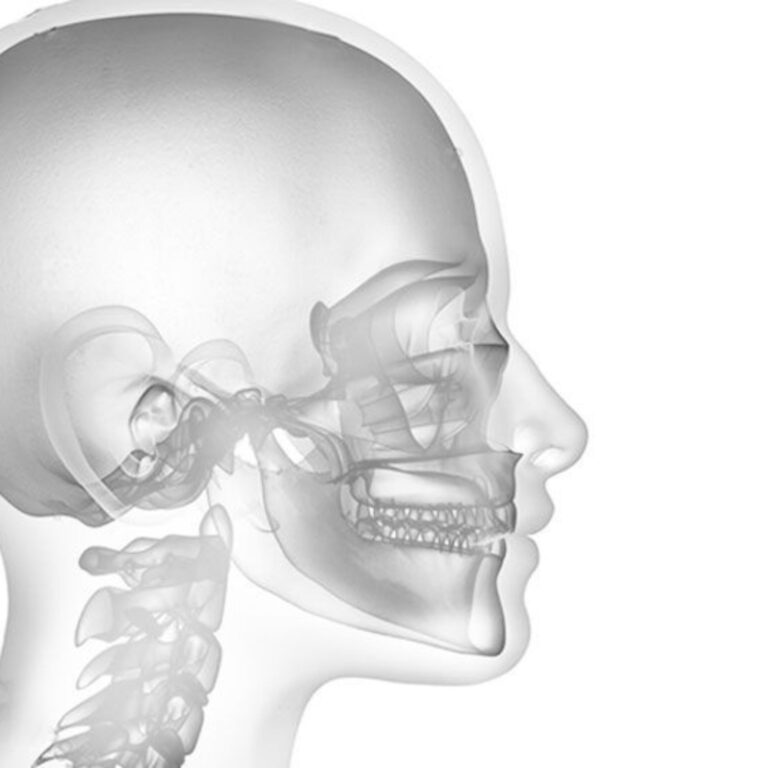

- Analyse des caractéristiques squelettiques du visage (céphalométrie)

- Radiographies 3D (tomographie volumique des maxillaires, des articulations, des voies aériennes, des dents incluses, des dents de sagesse, etc.)

- Imagerie par résonance magnétique (IRM) de l’articulation temporo-mandibulaire (si nécessaire) Étude de l’occlusion par électromyographie des muscles masticateurs (si nécessaire).